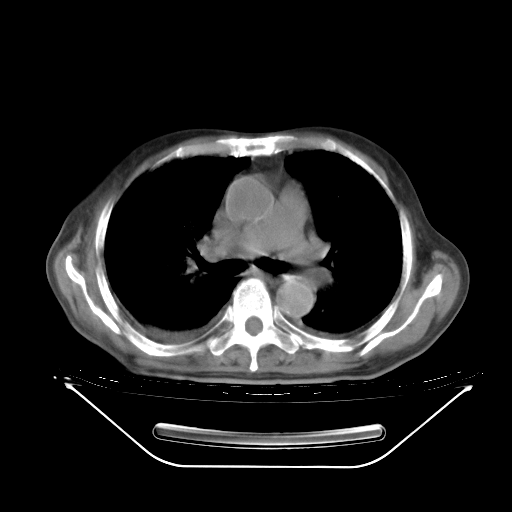

5月9日肺部CT(在4月27日齐鲁医院肺部CT描述部分肺组织磨玻璃样改变,12天后肺组织广泛磨玻璃样改变)

2009年5月9日肺部CT

大致读了系列胸部CT:纵隔窗无明显异常,肺窗:从4、27至今:主要是双肺中下野外带可见毛玻璃样改变,目前处于急性肺泡炎阶段,至于原因考虑1、结替组织或胶原血管性疾病所致?2、恶性疾病如恶组在肺部所致的表现或细支气管肺泡癌?3、药物或其它原因如肺蛋白沉着症所致肺泡炎目前不太可能?总之,明天就去请我院的呼吸科、感染科、血液科和临免专家会诊哈。